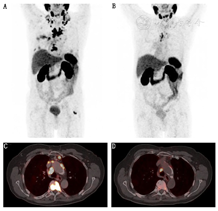

每一疗程后应检测PSA水平以评估患者对治疗的响应。影像学检查(如CT或PSMA PET/CT),应在每2个疗程后进行1次(图3)。177Lu-PSMA的RLT响应标准尚未明确界定。前列腺癌临床试验工作组3的标准可作为评价177Lu-PSMA的RLT响应的合理参考[44],但是否进行重复RLT应根据患者个体对治疗的响应(包括临床症状和生活质量)来决定[16,17]。